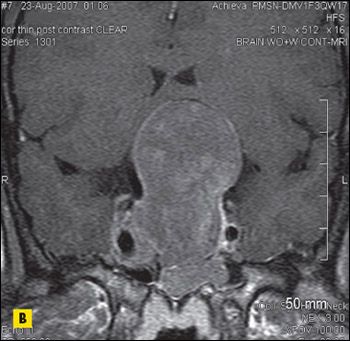

MRI scans of the brain revealed a 6 × 6 × 4-cm sellar mass with suprasellar and parasellar extension encasing the right cavernous sinus and carotid artery (Figure 2), which explained the vision loss.

Figure 2 – Sagittal (

A

), coronal (

B

), and axial (

C

) postcontrast MRI scans of the brain revealed a sellar mass of 6 × 6 × 4 cm with suprasellar and parasellar extension encasing the right cavernous sinus and carotid artery.